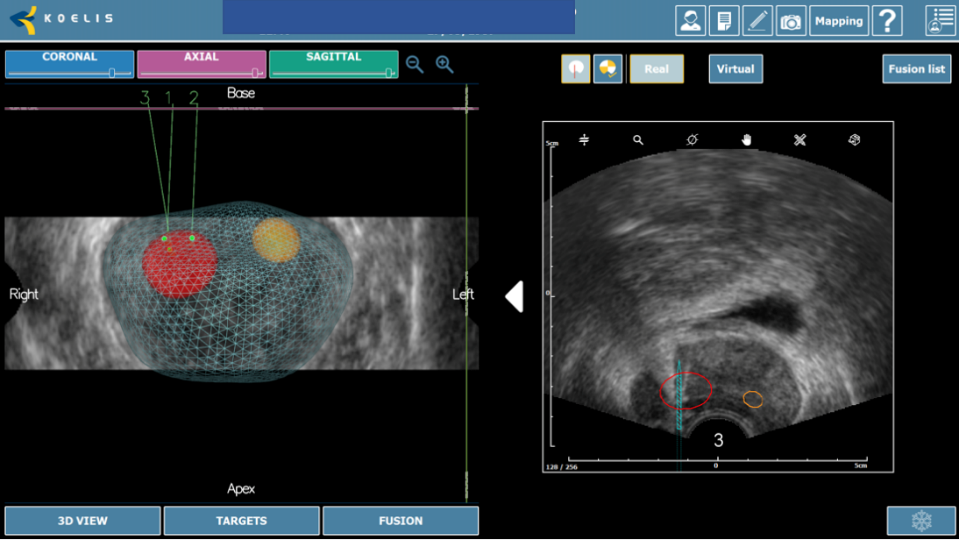

Biopsia de próstata por fusión guiada por TRUS-MRI

La siguiente innovación tecnológica de la biopsia de próstata guiada por resonancia ha sido el advenimiento de la fusión (o «registro») de hardware y software que permite la orientación en tiempo real al registrar y superponer las imágenes de mpMRI mapeadas previamente adquiridas en las imágenes TRUS durante la biopsia. Típicamente, esto se hace delineando (o «mapeando») el margen de próstata y la lesión sospechosa en las imágenes de mpMRI. Estas imágenes se transfieren posteriormente a una estación de trabajo especializada. TRUS toma imágenes de todo el volumen de la próstata, y el software fusiona las imágenes de resonancia magnética y de ultrasonido de la próstata mediante el uso de los límites como una guía (utilizando un método fijo y / o flexible). Posteriormente, el hardware monitorea la posición de la sonda TRUS con respecto a la próstata y puede proporcionar imágenes en tiempo real para alinear la biopsia con el sitio registrado de la lesión objetivo. (Figura 4)

Fig. 4. Biopsia por fusión. Imagen de fusión con objetivo (izquierda). Tecnología organ based tracking para control del disparo (derecha)

La próstata se escanea con la sonda de US. El operador define los contornos de la próstata y delinea las lesiones sospechosas a tratar en las imágenes de Resonancia. Los límites de la próstata se definen en la imagen en tiempo real de la próstata obtenida con la sonda trans-rectal del dispositivo. El software ejecuta automáticamente una «fusión elástica» de los dos volúmenes definidos, lo que conduce a una combinación tridimensional (3D) perfecta del volumen de RM con el volumen de la próstata en US. La misma fusión 3D se aplica al área sospechosa previamente identificada en la resonancia magnética y/o Biopsia por fusión que, por lo tanto, se puede identificar correctamente en la imagen en vivo de US. (Figura 7-8).

Fig. 7. Reconstrucción 3D biopsia por fusión, con cilindros negativos para cáncer(verdes), positivos (rojos) y área sospecha marcada en resonancia (amarillo).